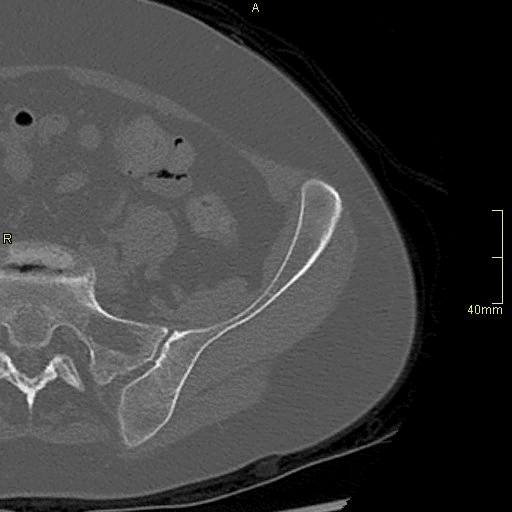

CT Hip Contrast- Soft tissue window (axial)

CT Hip Contrast- Bone window (axial)

CT Hip Non Contrast- Bone window (axial)

CT Hip Non Contrast- Soft tissue window (axial)